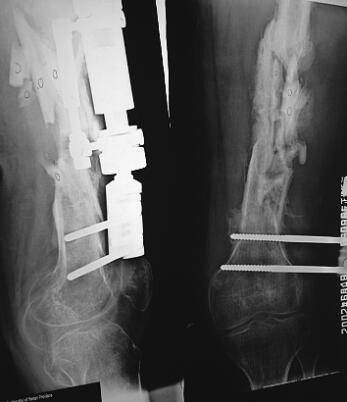

查体:发热39℃。右大腿中段明显红肿,肤温高;前外侧有长约25cm、5cm的2个伤口痕,周围有4个窦道痕,其中2个仍有稀薄脓性液,味腥臭;触诊局部肌肉无弹性,明显骨异常活动;膝关节僵直,髋关节功能明显受限,足部感觉、运动及血循正常。拍摄X线片(图3),示右股骨骨折单边支架固定术后,四枚螺钉无退钉现象;股骨中段呈严重粉碎性骨折,较多的骨折块硬化形成死骨,无明显连续性骨痂生长。血常规示WBC为14×109,ESR为60mm/h。入院诊断为右股骨骨折术后感染性骨不连、膝关节僵直。

图3 伤后4个月X线片